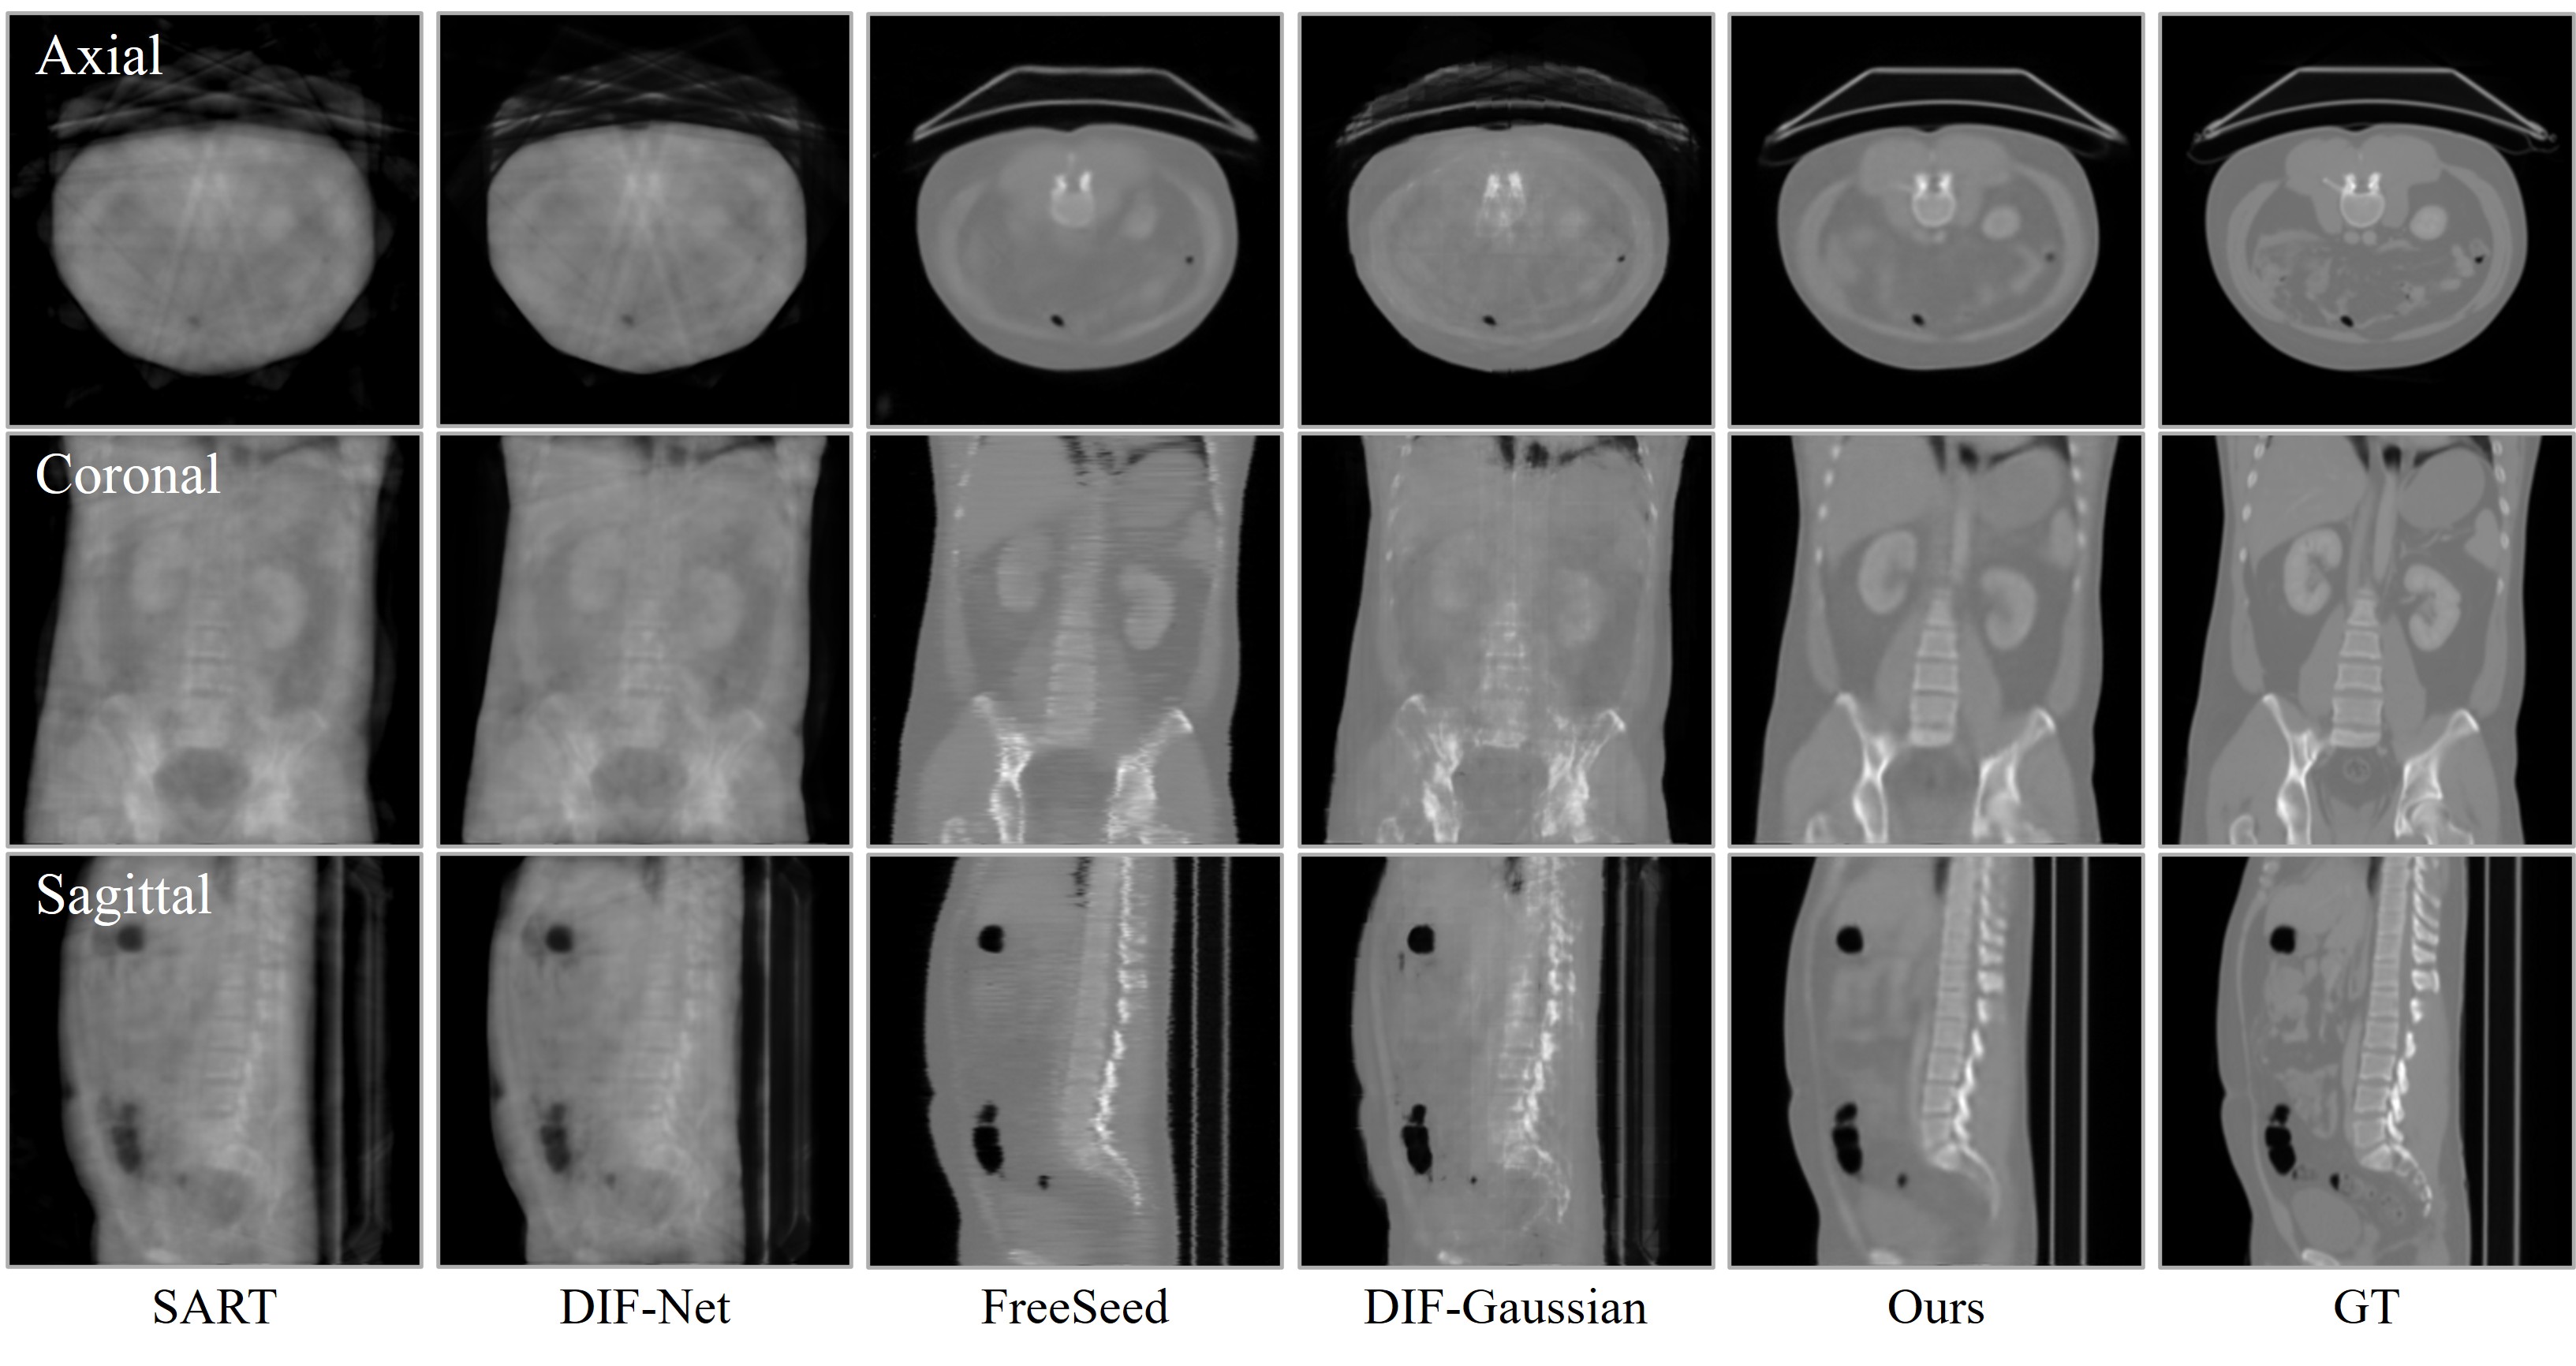

Visual comparison of CT reconstruction across different views. ILV achieves significantly cleaner structural details and consistency under both 10-view and 24-view sparse settings compared to existing methods.